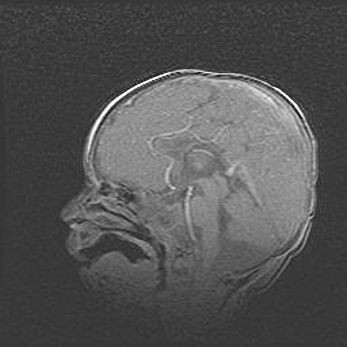

Наружная гидроцефалия с возможной атрофией височных областей.

Возраст: 28 дней

Вес: 3670 г

Пол: мужской

Окружность головы: 38 см

Срок гестации: 40 недель

Гидроцефалия головного мозга у новорожденных – это заболевание, которое характеризуется скоплением избыточного количества спинномозговой жидкости в желудочковой системе головного мозга в результате затруднения её перемещения от места выработки к месту поглощения в кровеносную систему или вследствие нарушения абсорбции. При открытой наружной форме гидроцефалии у новорожденных расширяются и переполняются субарахноидные пространства.

При нормотензивных  формах,  которые,  как  правило,  являются  следствием  перенесенных ишемических  повреждений  паренхимы  мозга,  возможно  сочетание микроцефалии  с нормотензивной гидроцефалией. В основе данных изменений лежит атрофия больших полушарий с преимущественной  локализацией  в  лобно-височных  областях.